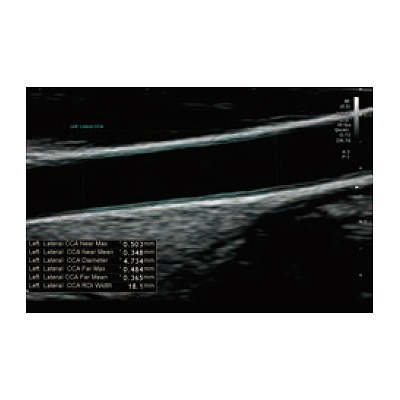

●動脈硬化の評価やシャントにおける機能評価も簡便に